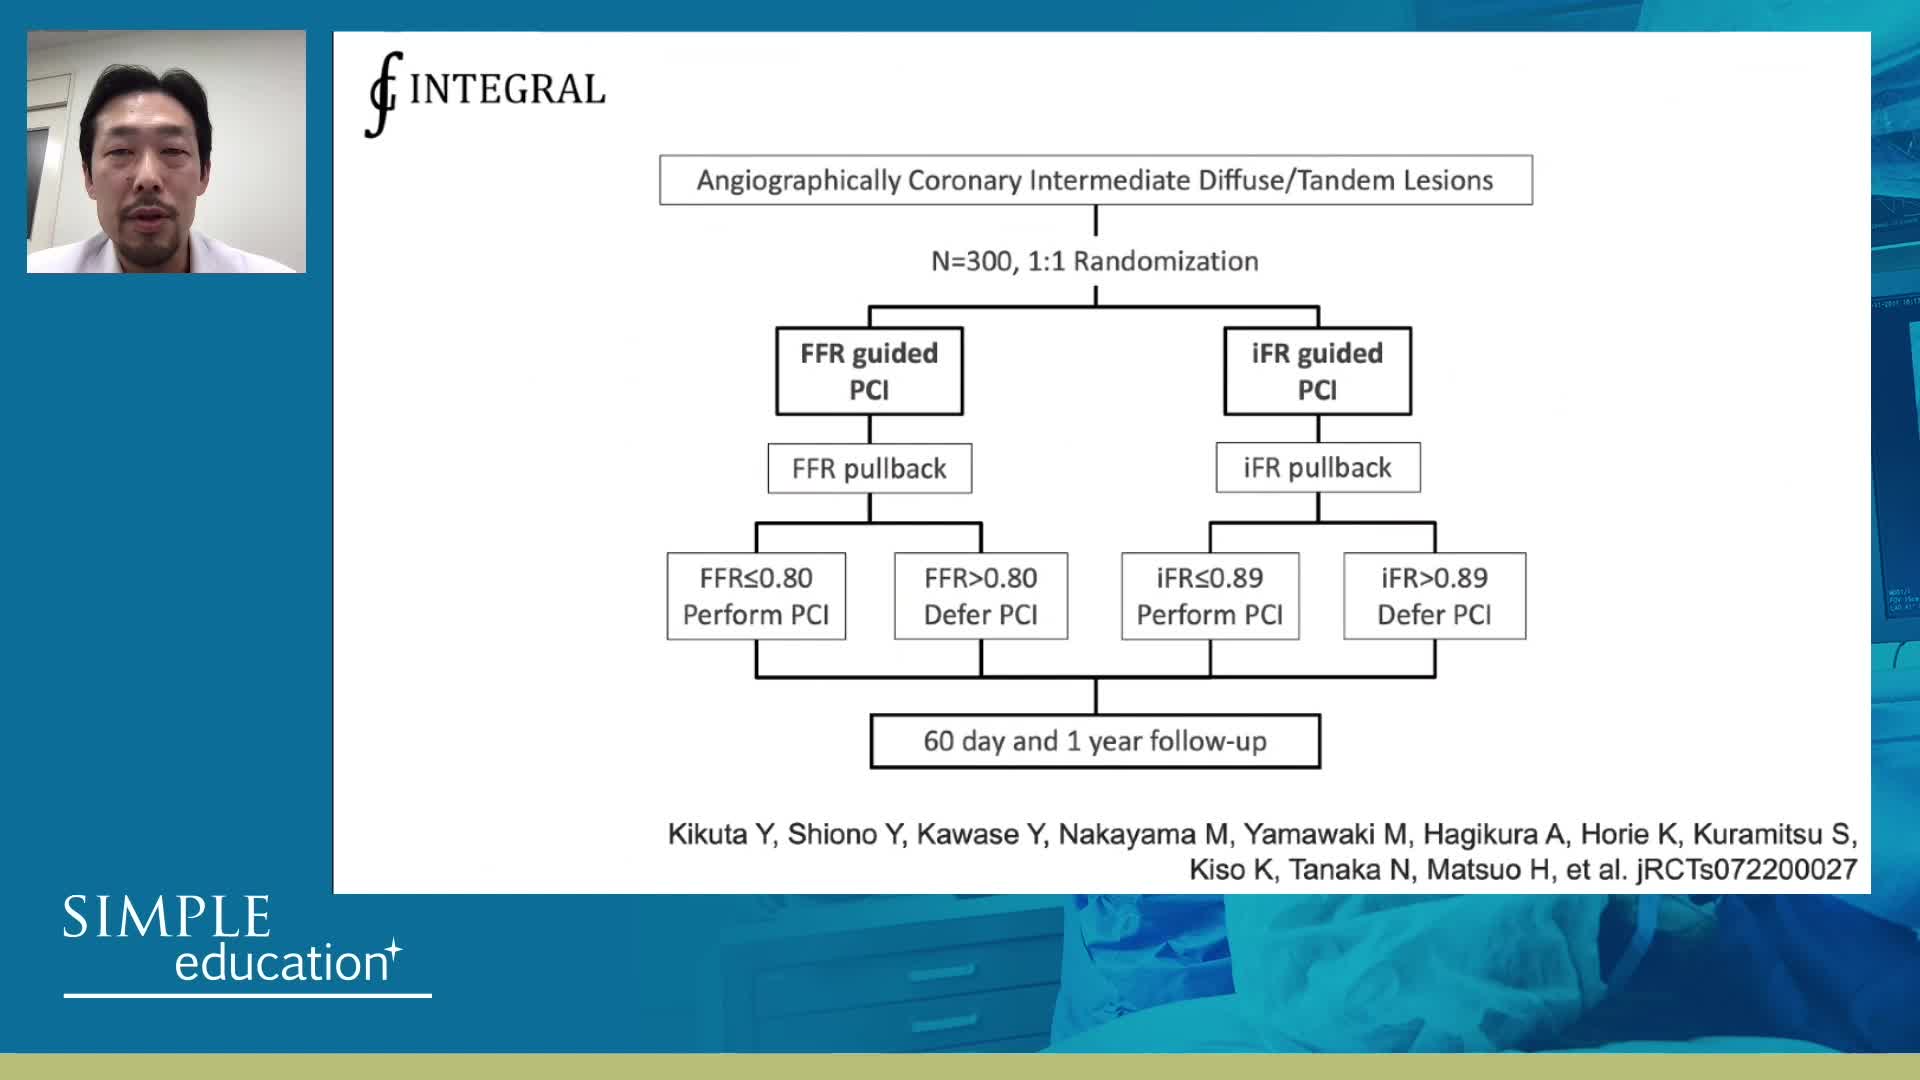

Advances in Co-registration, Coronary Physiology & Intra Coronary Imaging - April 2024 Day One

Advances in Co-registration, Coronary Physiology & Intra Coronary Imaging - April 2024 Day Two

Advances in Co-registration, Coronary Physiology & Intra Coronary Imaging - November 2023 Day One

Advances in Co-registration, Coronary Physiology & Intra Coronary Imaging - November 2023 Day Two

Advances in Co-registration, Coronary Physiology & Intra Coronary Imaging - November 2022 Day One

Advances in Co-registration, Coronary Physiology & Intra Coronary Imaging - November 2022 Day Two

Advances in Co-registration, Coronary Physiology & Intra Coronary Imaging - March 2022 Day One

Advances in Co-registration, Coronary Physiology & Intra Coronary Imaging - March 2022 Day Two